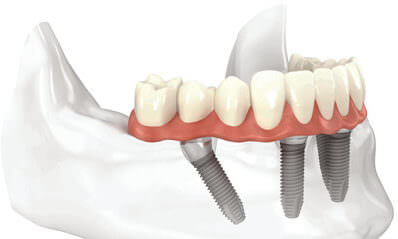

All-on-4 tedavi konsepti cerrahi operasyonla aynı günde 4 -6 implant üzerine sabit tam çene protetik restorasyonun yapıldığı tekniktir. Fonksiyon, estetik, tat, konuşma ve özgüveni dikkate alarak hasta memnuniyetini sağlar.

All-on-4 tedavisinde geleneksel implantlardaki titanyum vida mekanizması kullanılmaktadır. Geleneksel implantlarla All-on-4 implantlar arasındaki en büyük fark; ağız içinde nasıl konumlandırıldıklarıdır. Tamamen dişsiz olan bir çenede kayıp dişlerin yerine konmak üzere 8 ya da 10 implant kullanılırken bu yeni teknikle sadece 4 implant yeterli olur.

Ön kısımda, kemiğin en kalın olduğu yere 2 implant, çene kemiğinin arka kısmında ise 2 implant yerleştirilir. Öndeki implantlar 90 derecelik açıyla yerleştirilirken, maksimum sağlamlık sağlamak için arkadaki implantlar 45 derecelik açıyla yerleştirilmektedir. Bu 4 implant da yerleştirildikten sonraki adım, implantların üzerine köprü ya da kronlar yerleştirilir.

All-on-4 tedavisinde tedavi öncesi hastalardan alınan ölçüye göre geçici protezleri hazırlanır. Lokal anestezi altında hastanın çekilecek dişleri varsa bunlar çekilerek implantları yerleştirilir. Ölçü alınarak hazırlanan geçici protezler bu implantlara takılır. 3 ay sonra ise hastanın kalıcı protezleri takılır